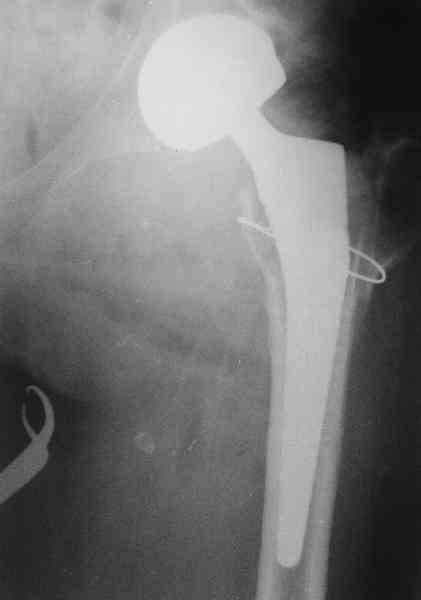

Re: несросшаяся шейка бедра

Не такое уж страшное укорочение по снимкам.Вчера прооперирован похожий случай.Обошлись без релиза и аппаратного низведения. укорочение было 4 сантиметра.Теперь ножки ровные.